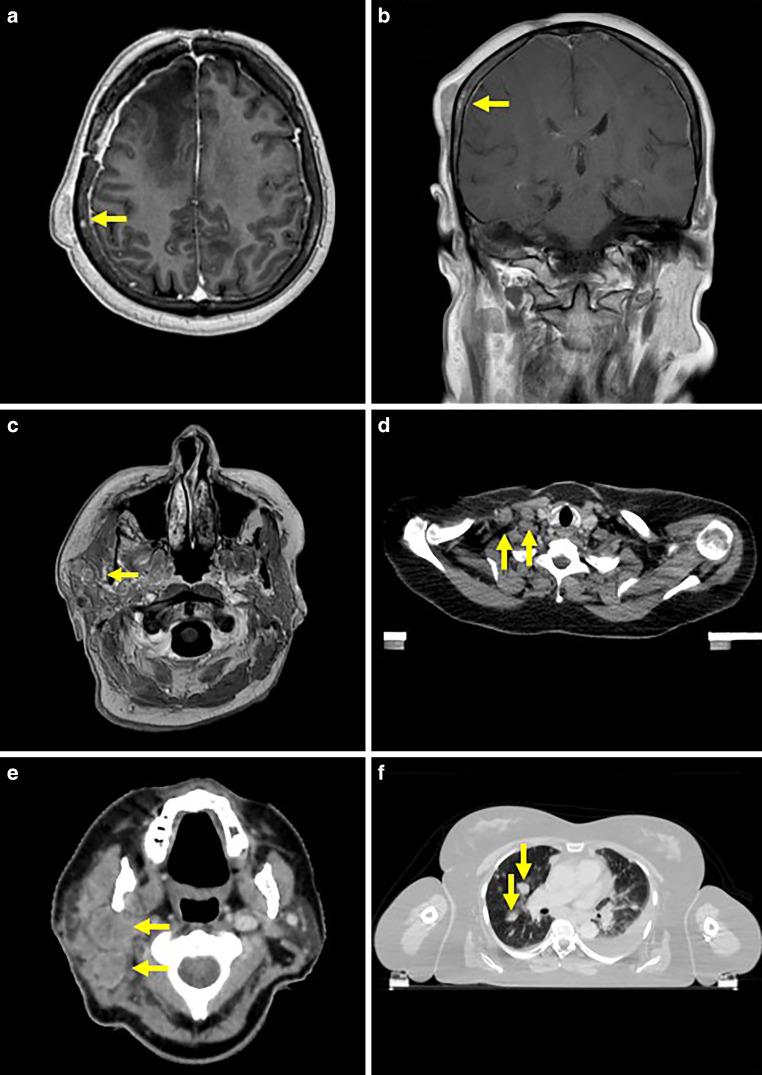

We conducted a systematic literature review in the PubMed database and complemented the data by inclusion of a case treated in our clinic. In this context, we report on a 60-year-old woman with a right frontal glioblastoma, IDH wildtype, MGMT methylated.

Six months after initial diagnosis and primary treatment, there was extensive local intracranial progression with additional extension into the subcutaneous and frontotemporal cranial bones. Despite continuation of multimodal treatment, further extracerebral manifestations occurred 11 months after the initial diagnosis, both in the cranial bone as well as metastases in the right parotid gland, cervical lymph nodes, and lungs. While local radiotherapy enabled the cerebral lesions to be controlled, the patient's clinical condition deteriorated rapidly despite simultaneous systemic therapy. The treatment had to be discontinued, and the patient died 5 weeks after confirmation of the multilocal extracerebral manifestations and a total of 12 months after initial diagnosis.

初次诊断和初次治疗6个月后,颅内出现广泛的局部进展,并进一步扩展至皮下和额颞颅骨。尽管继续进行多模式治疗,但初次诊断11个月后出现了更多的脑外表现,包括颅骨以及右侧腮腺、颈部淋巴结和肺部的转移。虽然局部放疗使脑部病变得到控制,但尽管同时进行了全身治疗,患者的临床状况仍迅速恶化。治疗不得不中断,患者在确认多部位脑外表现后5周死亡,初次诊断后共计12个月。